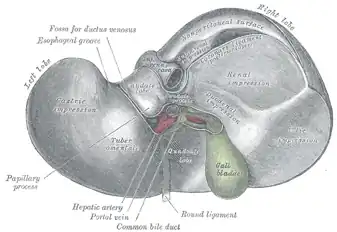

|

| Foie humain, vue inférieure |

Face viscérale

La face viscérale du foie occupe la partie inférieure du foie, dans le plan transversal, et regard en arrière, en bas et à gauche. Elle présente deux fissures sagittales et une fissure transversale qui lie ces dernières et forme un « H » :

- la fissure sagittale droite (ou sillon sagittal droit) correspond à la fosse de la vésicule biliaire en avant, et au sillon de la veine cave inférieur en arrière ;

- la fissure sagittale gauche (ou sillon sagittal gauche) est le sillon continu formé par la fissure du ligament rond en avant, et par la fissure du ligament veineux en arrière. Le ligament rond du foie est le reliquat fibreux de la veine ombilicale, qui transporte le sang bien oxygéné et riche en nutriments, du placenta au fœtus. Le ligament veineux est également un vestige, du conduit veineux, qui court-circuite la circulation hépatique et achemine ainsi les nutriments du placenta à la circulation systémique. Lors de la naissance, ces deux veines s’oblitèrent en tissu fibreux (ligaments) ;

- le sillon transversal relie en arrière les deux sillons sagittaux et forme le hile du foie (ou porte du foie), point de passage des vaisseaux vasculaires et lymphatiques, des nerfs et des conduits biliaires.

C'est donc par la face viscérale que rentrent et sortent des structures telles que des vaisseaux sanguins et lymphatiques, nerfs et conduits biliaires, au niveau de la porte du foie (hile hépatique) : la porte du foie sert de porte de rentrée pour l'artère hépatique propre, la veine porte hépatique et les lymphonoeuds hépatiques, et de point de sortie pour les conduits biliaires (conduit hépatique commun et cystique, formant le cholédoque à la sortie du hile).

La face viscérale présente deux petits lobes accessoires : le lobe carré et le lobe caudé.